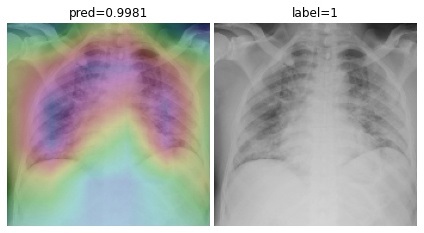

To overcome the aforementioned issues and force the model’s attention to the correct regions of interest (ROIs), we introduce the COVID-CXNet. Our model is initialized with the pretrained weights from CheXNet. A dataset of 3,628 images, 3,200 normal CXRs and 428 COVID-19 CXRs, are divided into 80% as training-set and 20% as test-set. Batch size is set to 16, rather than 32 in previous models, regarding memory constraints. Grad-CAMs of the COVID-CXNet for random images are plotted in Fig. 15.

Figure 15: Grad-CAM visualization of the proposed model over sample cases

More Grad-CAMs are available in Appendix A. Heatmaps are more accurate than previous models, while an accuracy of 99.04% and an f-score of 0.96 are achieved. Table 3 is the confusion matrix of the proposed model.